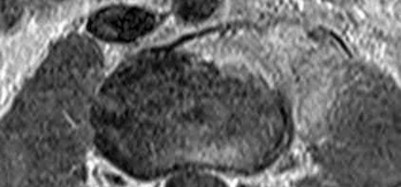

The safe zone for tibial nail placement as seen on radiographs is just medial to the lateral tibial spine on the anteroposterior radiograph and immediately adjacent and anterior to the articular surface as visualized on the lateral radiograph.

Tornetta et al specifically located the safe zone for nail entry in a study using fresh frozen cadaver knees. The authors found that the safe zone for nail placement is located 9.1+/-5 millimeters lateral to the midline of the plateau and three millimeters lateral to the center of the tibial tubercle. The width of the safe zone averaged 22.9 millimeters and was as narrow as 12.6 millimeters.

The starting point of the of the nail can be best viewed on the lateral knee radiograph, an example of which is shown in Illustration A. Illustration B shows the "sweet spot" for nail insertion as defined by Tornetta.